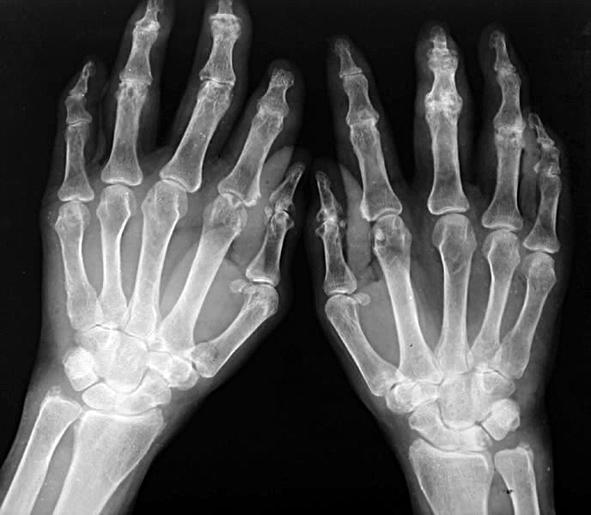

类风湿性关节炎是一种以侵蚀性关节炎为主要临床表现得自身免疫病,可发生于任何年龄,基本病理表现为滑膜炎、血管翳形成,并逐渐出血关节软骨和骨破坏,最终导致关节畸形和功能丧失,可并发肺部疾病、心血管疾病、恶性肿瘤及抑郁症等。

(7)手、腕关节X线显示有骨侵蚀或明确的骨质疏松。